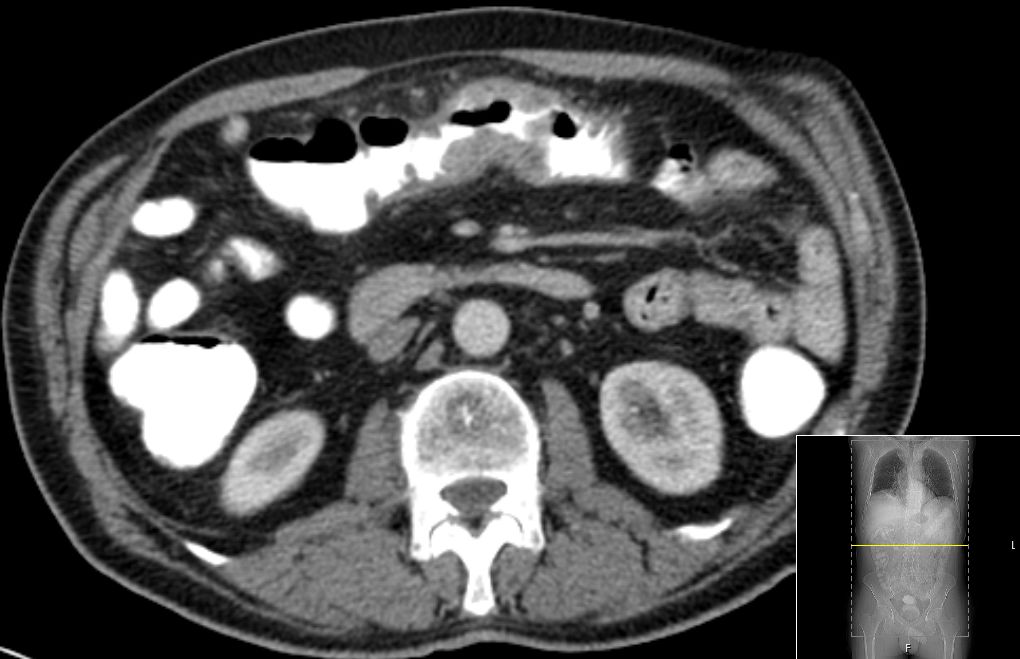

CT: Langstreckige Darmwandveränderungen mit einer hochgradigen Stenose des Colon transversums sowie mit diskreten Verdichtungen in dem umgebenden Gewebe.

Dorsale Harnblasenwandverdickung.

Verkalkungen der Prostata. Keine vergrößerten Lymphknoten![]() |

Operateur: Im Bereich des Quercolons, näher zur rechten Colonflexur, findet sich ein mannsfaustgroßer Tumor.Histologisch invasivem Adenokarzinom![]() | |